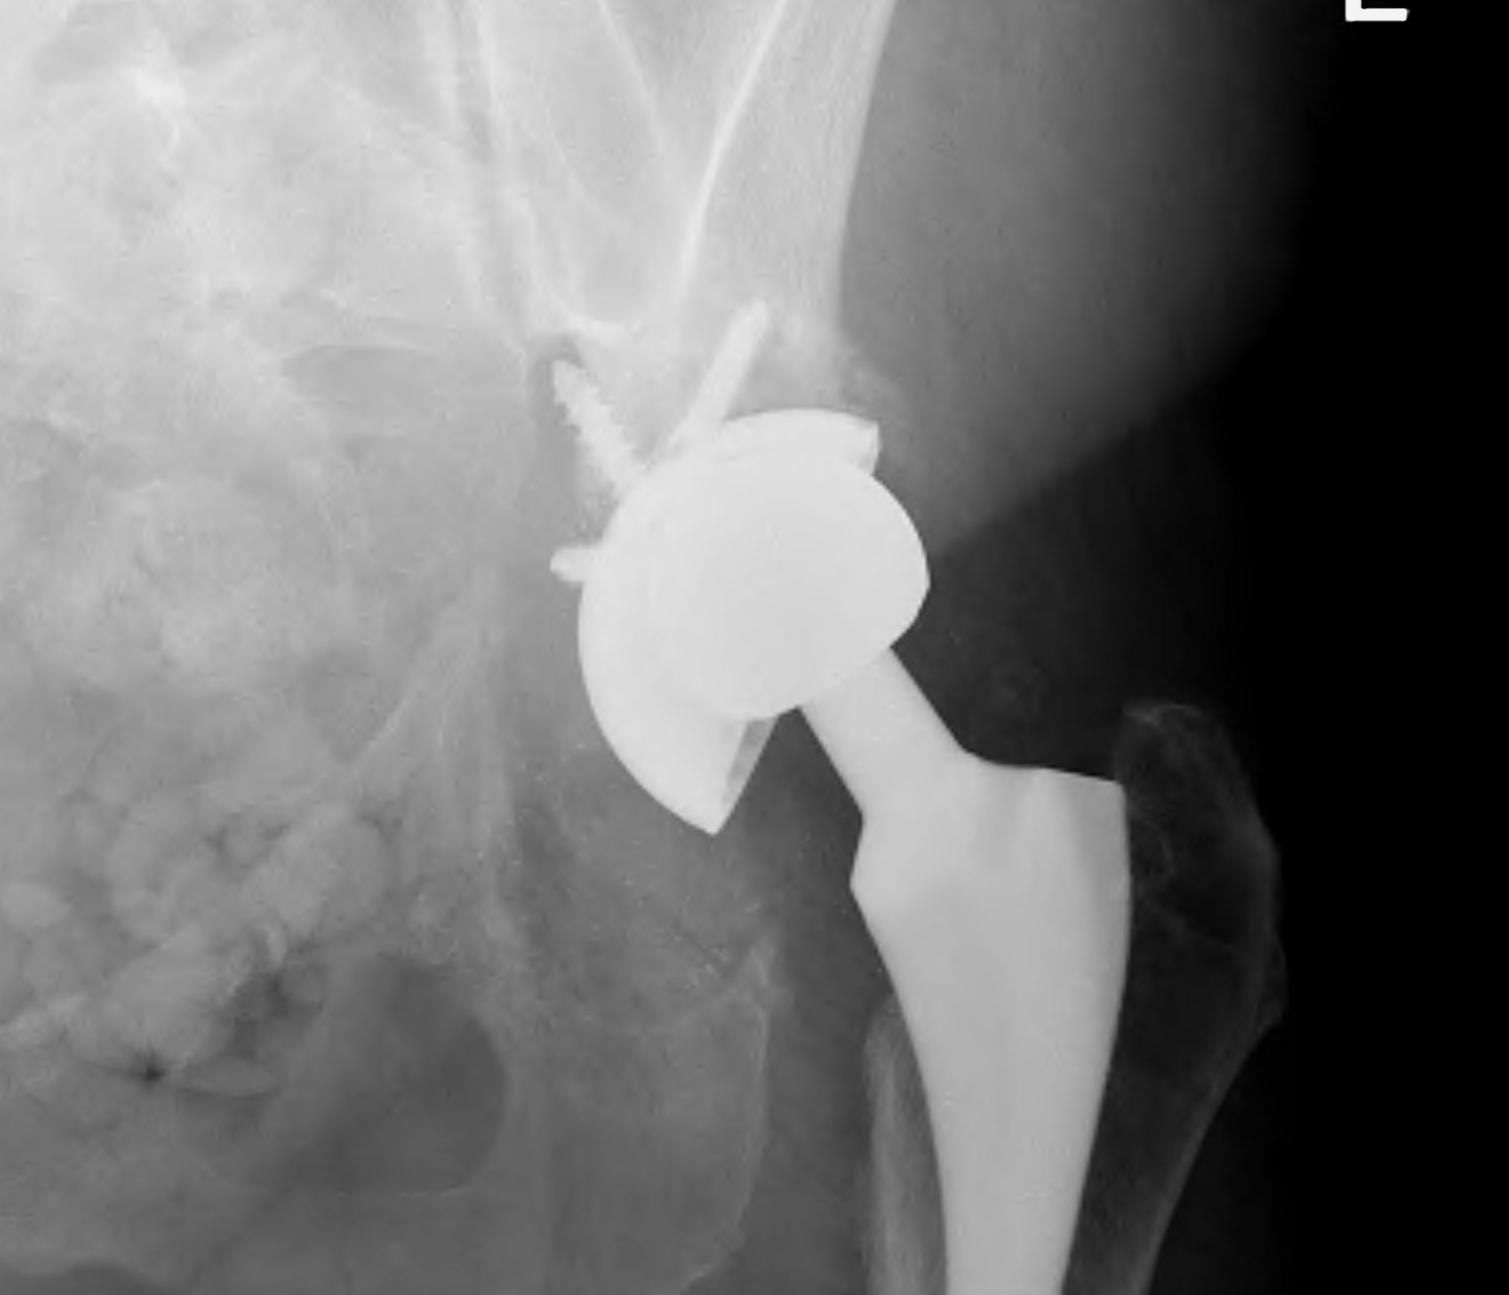

1. Structural Allograft + Cage

Indications

- when inadequate bone stock precludes the use of uncemented acetabular components

Theory

- cannot implant onto allograft

- graft under the cage

- secure with cage

- cement poly into it

Technique

- allograft reconstruction of rim with femoral head

- allograft particulate material in base

- secure cage to posterior column ilium and ischium

- 3 screws in each

- cement all poly cup into cage

Results

- 75% 10 – 15 year survival

Option: Custom-made triflange components

CT guided model of pelvis

- custom made acetabular cage

- fits defect exactly

- flanges perfectly designed and not malleable to improve strength

- HA coated

- cement poly cup into it

- massive defects

- 90% 4.5 year survival in complicated patients